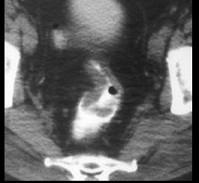

问题 男,53岁,便秘、血便,大便变细,CT如图,应考虑为 ( )

选项 A、慢性溃疡性结肠炎 B、直肠淋巴瘤 C、直肠结核 D、溃疡型直肠癌 E、肠crohn病

答案 D